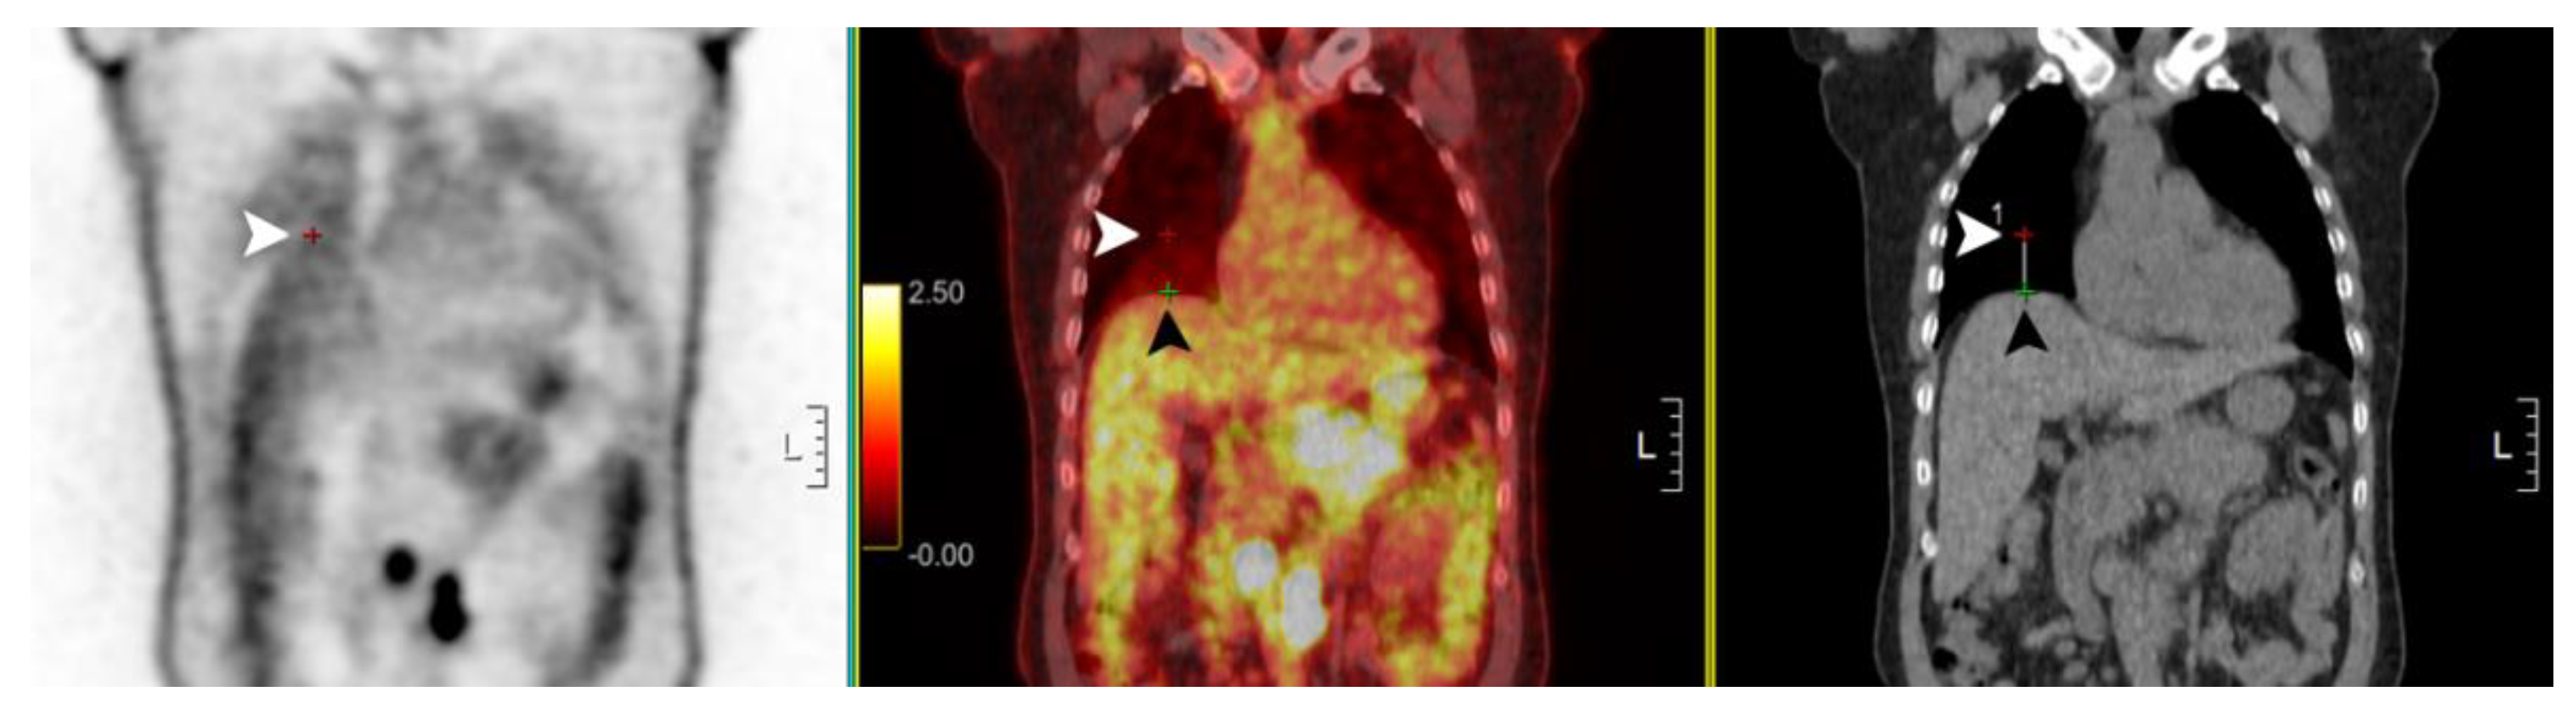

3. Results

4. Discussion